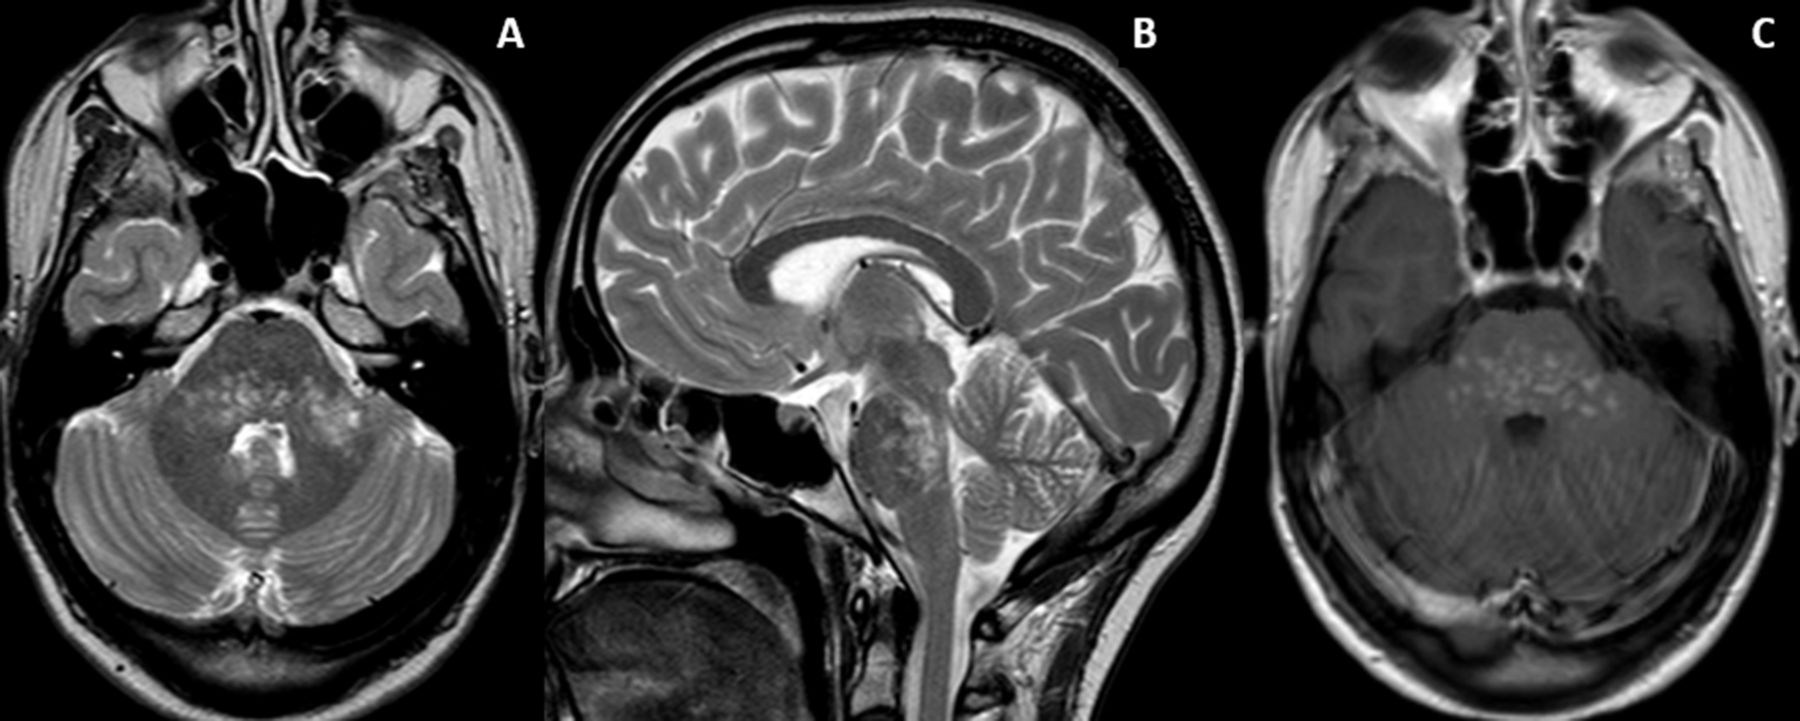

Clippers Syndrome / Clippers With Brain And Spinal Cord Involvement Eurorad / Clippers syndrome can occur at any age, ranging from 15 to 85 years with a mean age around the fifth decade 2.. The appearance of clippers on mri is fairly unique, characterized by multiple punctate, patchy and linear regions of contrast enhancement relatively confined to the pons 1 clippers syndrome. Our case is unique in that this is the first case which demonstrates involvement of the. Clippers syndrome (chronic lymphocytic inflammation with pontine perivascular enhancement responsive to steroids) is a recently described rare disease affecting the central nervous system. Clippers sendromu merkezi sinir sisteminin inflamatuvar bir hastalığıdır. In addition, we also present a unique case of newly described autoimmune entity clippers syndrome.

Klippel trenaunay syndrome in association with sturge weber syndrome about one case. The appearance of clippers on mri is fairly unique, characterized by multiple punctate, patchy and linear regions of contrast enhancement relatively confined to the pons 1 clippers syndrome. Clippers is a rare chronic inflammatory disorder of unknown cause that primarily affects the brainstem. Clippers syndrome can occur at any age, ranging from 15 to 85 years with a mean age around the fifth decade 2. It affects both genders with possibly a minor male predominance.